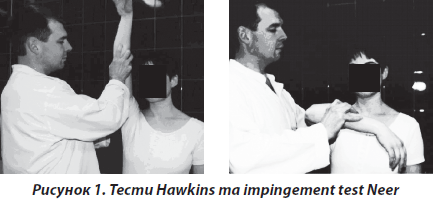

Синдром субакроміального конфлікту плеча спостерігався у 117 пацієнтів, середній вік 46 років (68 жінок та 49 чоловіків). Хворі скаржились на біль в еполетній зоні плеча під час рухів та вночі. Захворювання характеризувалось безпричинним, поступовим розвитком. Невелика кількість хворих (11 %) вказували на травму в анамнезі, проте переважна більшість (89 %) пов’язують розвиток захворювання з хронічним перевантаженням. Більшість хворих (73 %) до моменту обстеження проходили консервативне лікування з приводу остеохондрозу шийного відділу хребта. При огляді відмічалось западання надостної та підостної ямок лопатки з боку ураження, що трактувалось нами як гіпотрофія відповідних м’язів. У всіх хворих відмічалось порушення плечелопаткового ритму, що встановлювалось нами на підставі різниці у відстані між лопатками та остистими відростками грудного відділу хребта під час виконання симетричних абдукційних рухів. Відмічався біль при пальпації великого горбка, передньозовнішньої поверхні акроміального відростка лопатки. У хворих даної групи були позитивними тести Hаwkins, імпінджмент-тести [13] (рис. 1).

Третю групу хворих становили 152 пацієнта зі скаргами на біль в еполетній зоні плеча з іррадіацією до верхньої третини передпліччя. У 132 хворих біль мав характер хронічного, постійного, ниючого, гризучого, що посилювався при відведенні плеча в межах 70–120°. Захворювання у них розвивалось поступово протягом декількох місяців або років. Точніші дані навести неможливо через те, що пацієнти не могли уточнити дату початку захворювання, що ще раз свідчить про його поступовий розвиток. Проте у 20 пацієнтів захворювання розпочалось із різкого болю вказаної локалізації, що мав характер сіпаючого, прострільного, больовий синдром різко обмежував рухи в кінцівці. У хворих були позитивні тести Hаwkins, імпінджмент-тест (рис. 1). На рентгенограмах відмічались вогнища затемнення в проекції місця прикріплення сухожилка надостного м’яза без контакту з великим горбком (рис. 5).